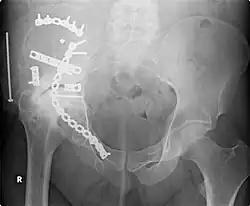

Orthopedic surgery or orthopedics (alternative spelling orthopaedics) is the branch of surgery concerned with conditions involving the musculoskeletal system.[1] Orthopedic surgeons use both surgical and nonsurgical means to treat musculoskeletal trauma, spine diseases, sports injuries, degenerative diseases, infections, tumors and congenital disorders.

- Orthopedic trauma

- Repair of femoral neck fracture

- Repair of trochanteric fracture

- Repair of femoral shaft fracture